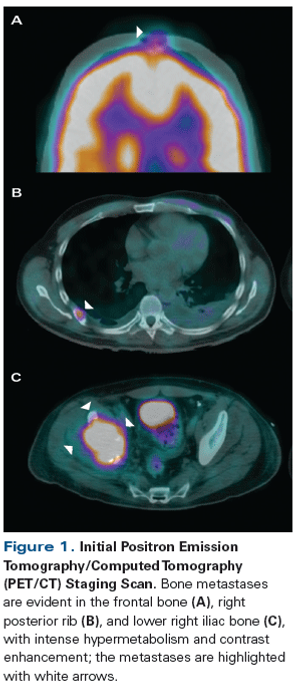

A 42-year-old man presented with increasing right hip pain that limited his ability to walk. Magnetic resonance imaging (MRI) revealed a right lytic acetabular lesion. Further work-up included a computed tomography (CT) scan, which revealed an 8-cm left kidney tumor.